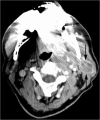

Carotid sinus syndrome is a serious manifestation of head and neck malignancy. The purpose of this study was to clarify the presence of carotid sinus syndrome in a patient with cystadenolymphoma. To our knowledge carotid sinus syndrome secondary to cystadenolymphoma has not been reported to date. A 45-year-old woman with one-week-old swelling in the left mandibular angle having disturbing symptoms of vertigo, consciousness and sinus arrest. Holter monitoring revealed several episodes of sinus arrest. Ultrasonography showed a well-defined space-occupying lesion of about 31 mm in length and 17 mm in width located in the deep lobe of the left parotid gland. Computerized tomography (CT) showed a large mass extending into the carotid space and protruding into the parapharyngeal space. Parotidectomy was performed. Surgical removal of the tumor resulted in complete amelioration of symptoms and disappearance of electrocardiogram abnormalities. Here we report on a clinical case of carotid sinus syndrome associated with cystadenolymphoma. To our knowledge carotid sinus syndrome secondary to cystadenolymphoma has not been reported to date, and is made more remarkable as a possible differential diagnosis after clarification of all possible causes. Early diagnosis and immediate management can minimize complications.